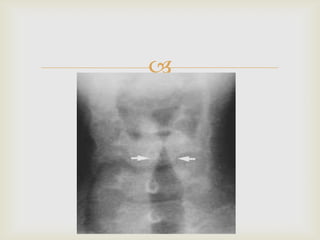

 DIAGNOSIS

 MAINLY A CLINICAL DIAGNOSIS

 RADIOGRAPH NECK :- STEEPLE SIGN

(UNRELIABLE)